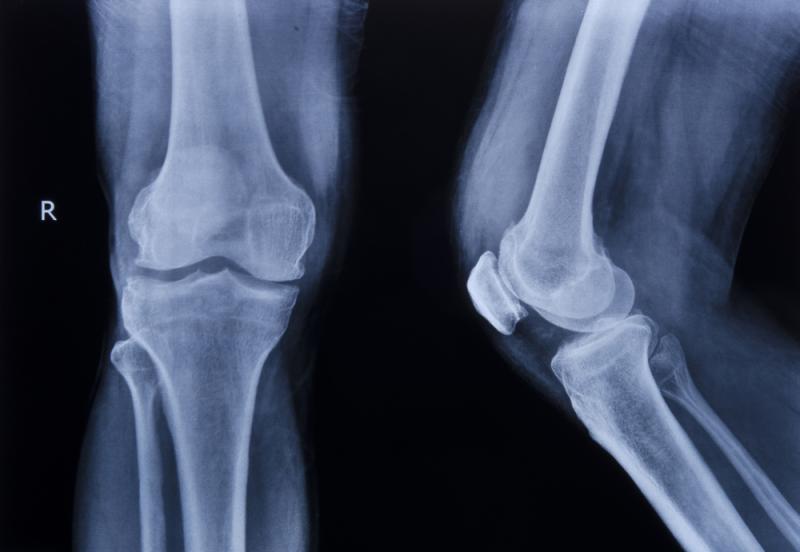

Budowa kolana

Aby zrozumieć skąd mogą brać się bóle w kolanie, należałoby zacząć od anatomicznej analizy jego struktury. W stawie kolanowym łączą się bowiem aż trzy kości: kość udowa, kość piszczelowa oraz rzepka. Ta ostatnia jest dość nietypowa – ma lekko trójkątny, spłaszczony kształt. Całość opleciona jest bardzo skomplikowanym aparatem mięśniowo-więzadłowym, na który składa się aż 5 więzadeł zewnątrzstawowych, 5 więzadeł wewnątrzstawowych, 8 kaletek maziowych oraz dwie łąkotki. Ruch stawu jest kombinacją toczenia i ślizgania się poszczególnych powierzchni, a jego zakres wynosi nawet do 170°. Nawet gdy stoisz, staw kolanowy poddany jest ciągłemu obciążeniu dyktowanemu przez prostujący mięsień czworogłowy uda i cały zestaw mięśni zginających. Amortyzację, bez której nie byłbyś w stanie wykonać wygodnie jednego kroku, zapewnia kolanu chrząstka stawowa. Aż trudno więc uwierzyć, że niektórzy z nas po 30 latach życia nie mają z kolanami problemów!